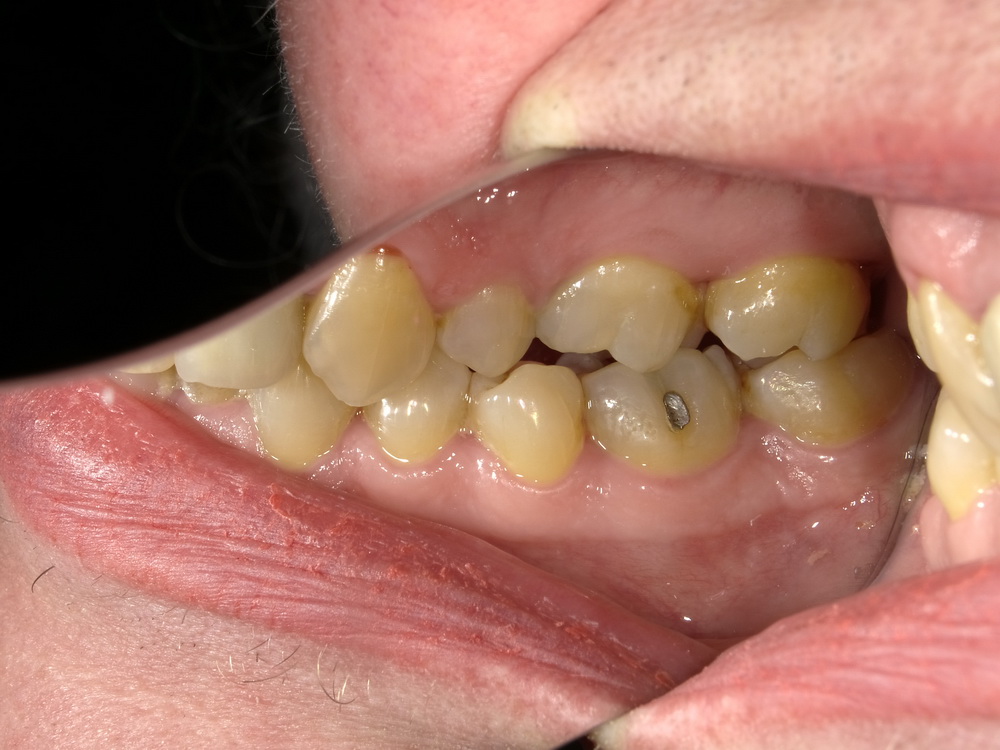

CMD-Patientin ausdem Schaumburger Land beginnt mir der Funktionstherapie

Nun soll es losgehen, was in den vergangenen Monaten systematisch vorbereitet wurde.

Es beginnt mit der Versorgung der Oberkieferseitenzähne mit Laborgefertigten Dauerprovisorien.

Das war der Zustand im September 2025.